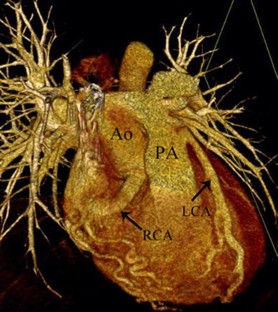

Fig. 2